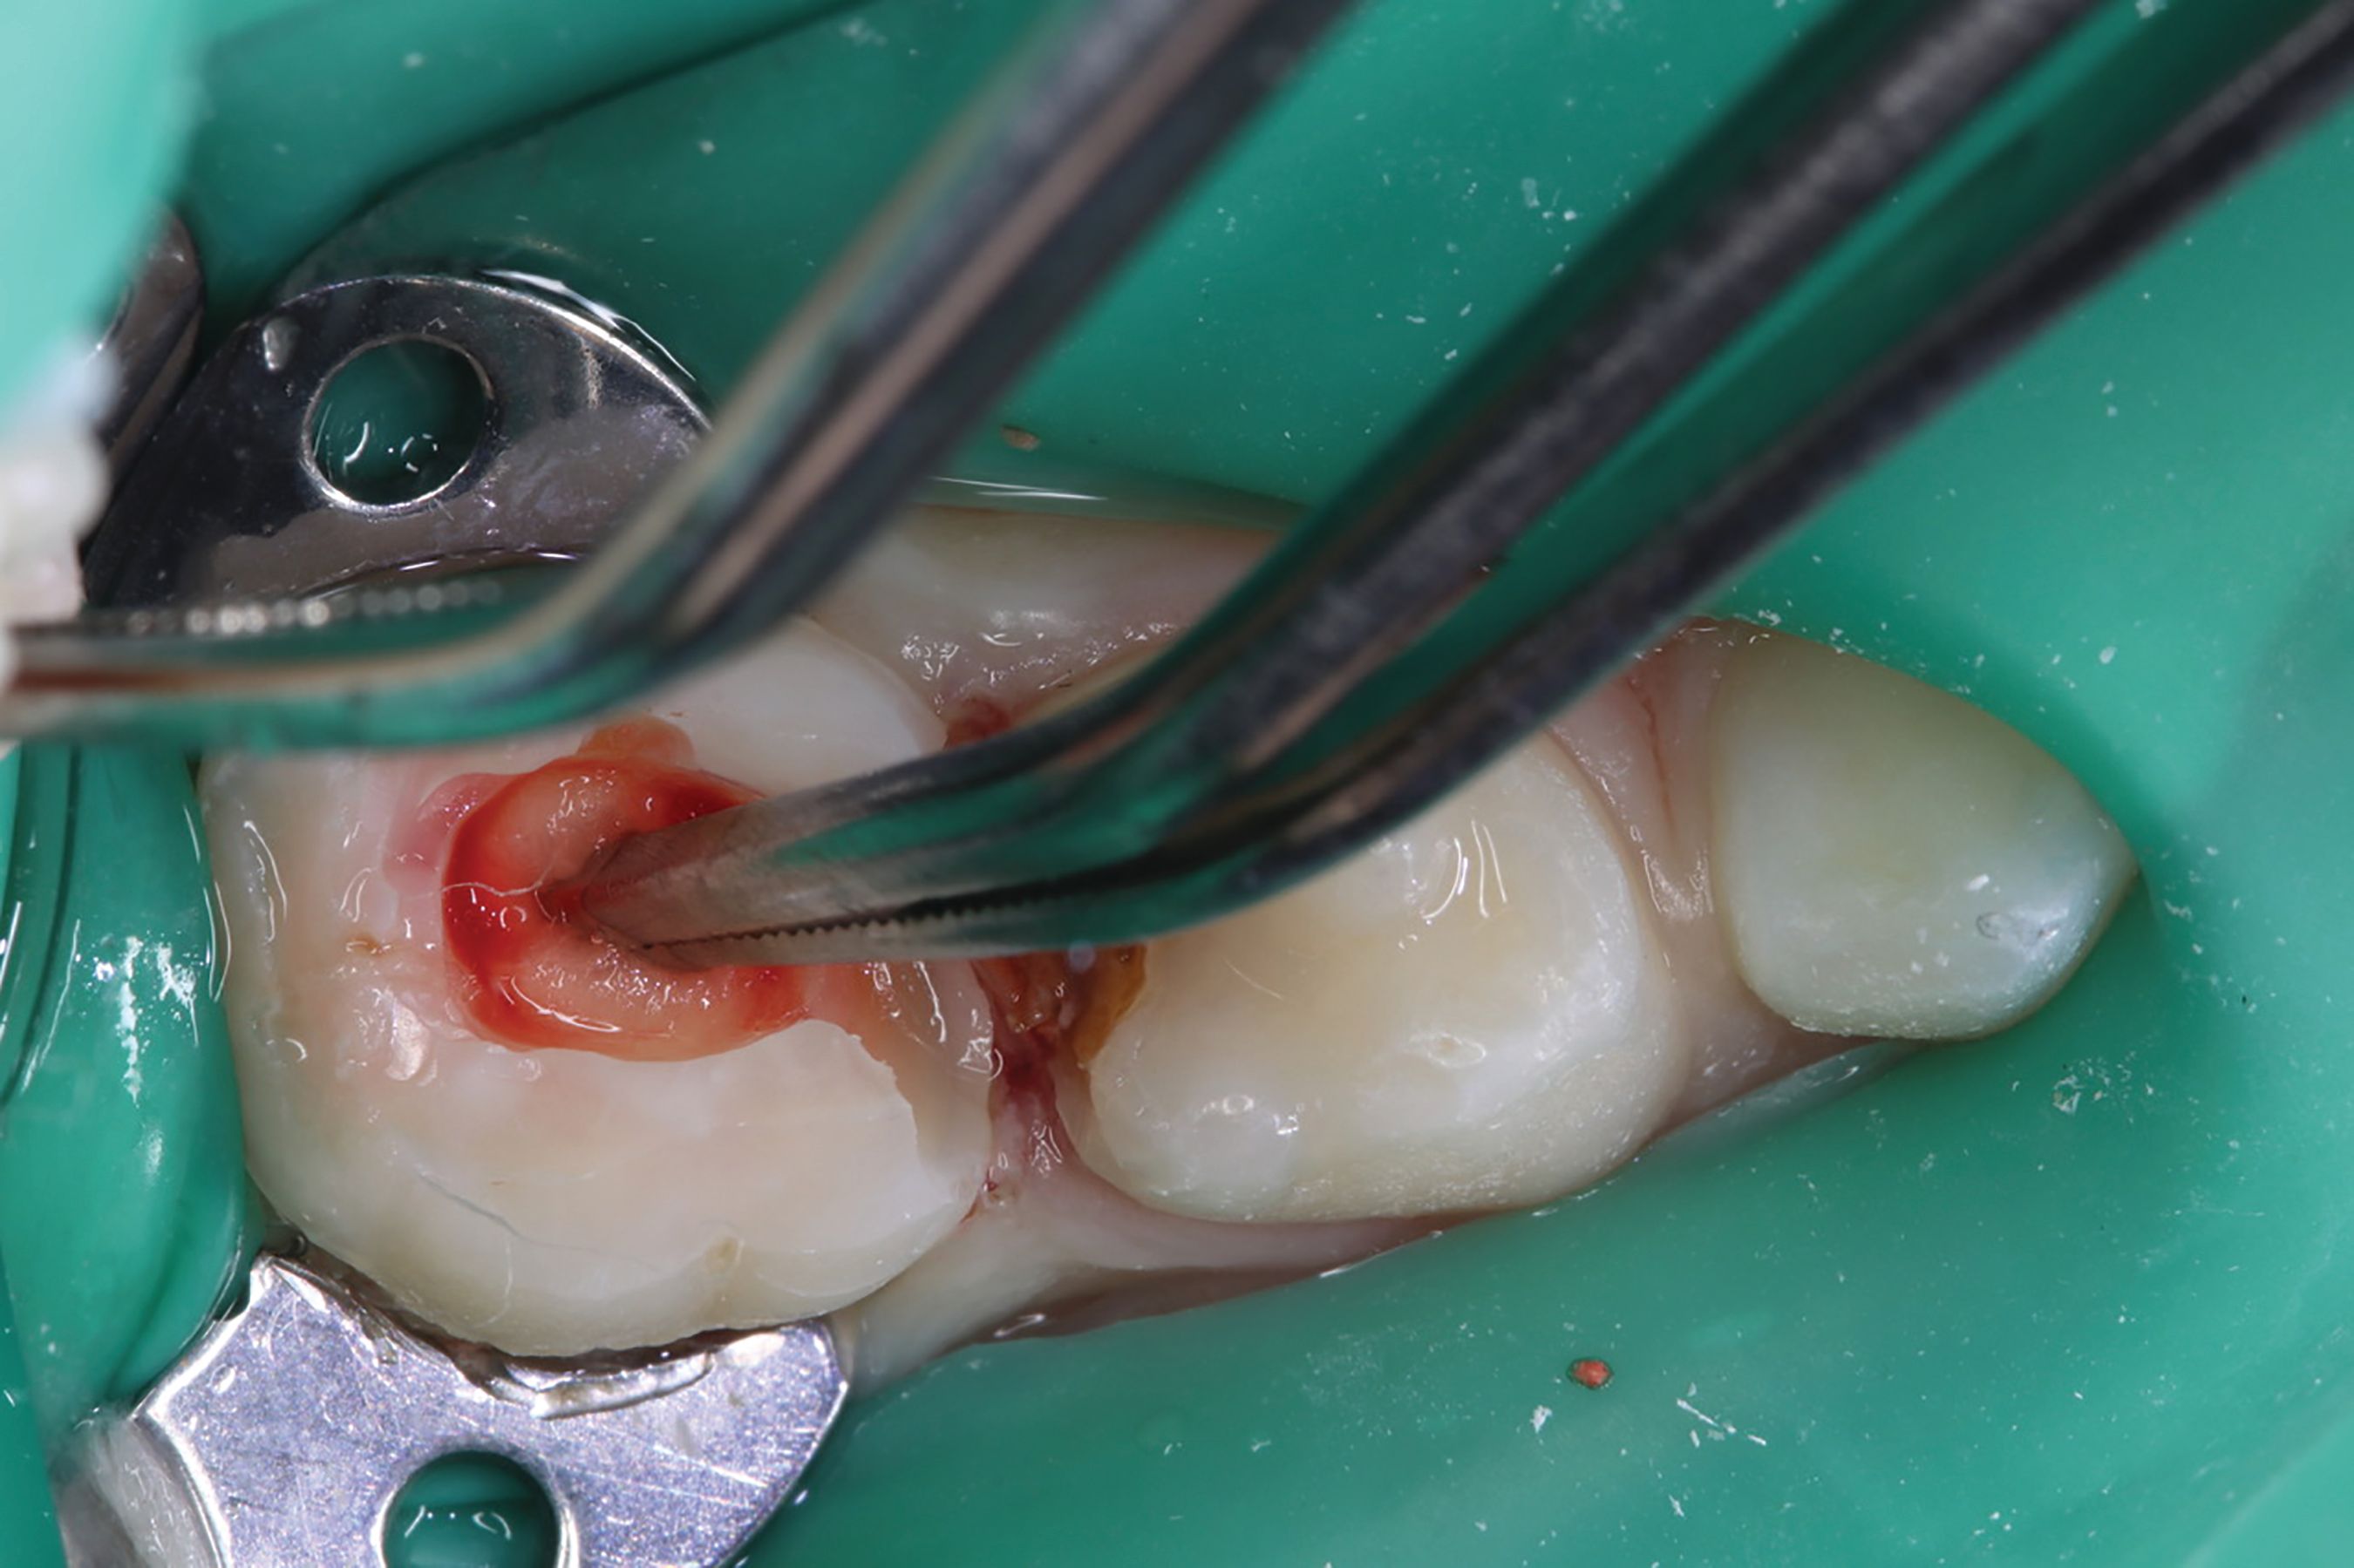

Amputation of coronal pulp chamber to the level of radicular pulp stumps was performed with NSK Dental slow speed large round bur #8, removing coronal pulp tissue with gentle upward motion (Fig. 2). Hemostasis is achieved with a saline-soaked sterile cotton pellet (Figs. 3-4). Figure 5 also illustrates hemostasis.

Fig. 4

Fig. 5

[ Figs. 1-9 ] Pre-operative view-primary second molar requiring pulpotomy procedure (Fig. 1). Amputation of coronal pulp chamber to level of radicular pulp stumps with NSK Dental’s slow speed large round bur #8, removing coronal pulp tissue with gentle upward motion (Fig. 2). Hemostasis achieved with saline-soaked sterile cotton pellet (Figs. 3 & 4). Hemostasis achieved (Fig. 5). Extrusion of TheraCal PT into pulp chamber, being sure to reach base of coronal pulp chamber with material and without voids or bubbles and light cure (Figs. 6 & 7). Cured TheraCal PT (Fig. 8). Full-coverage stainless-steel crown (Fig. 9).